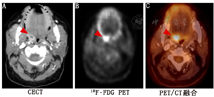

标记WBC显像是另1种可考虑的方法,尽管研究者认为其对那些高度怀疑感染的患者是准确的,尤其是对于术后患者[46],但多项使用WBC诊断FUO的研究却显示其灵敏度和诊断率低,特别是与18F-FDG PET/CT比较时[13,44,47]。尽管许多研究已表明了18F-FDG PET/CT在FUO诊断中的优势,但在18F-FDG PET/CT无法获得使用的情况下,仍可采用67Ga-枸橼酸盐和WBC显像[13,47]。图4为1例转移癌患者在18F-FDG PET/CT检查中偶然发现了扁桃体脓肿,显示出该法对隐匿性感染灶的定位能力。